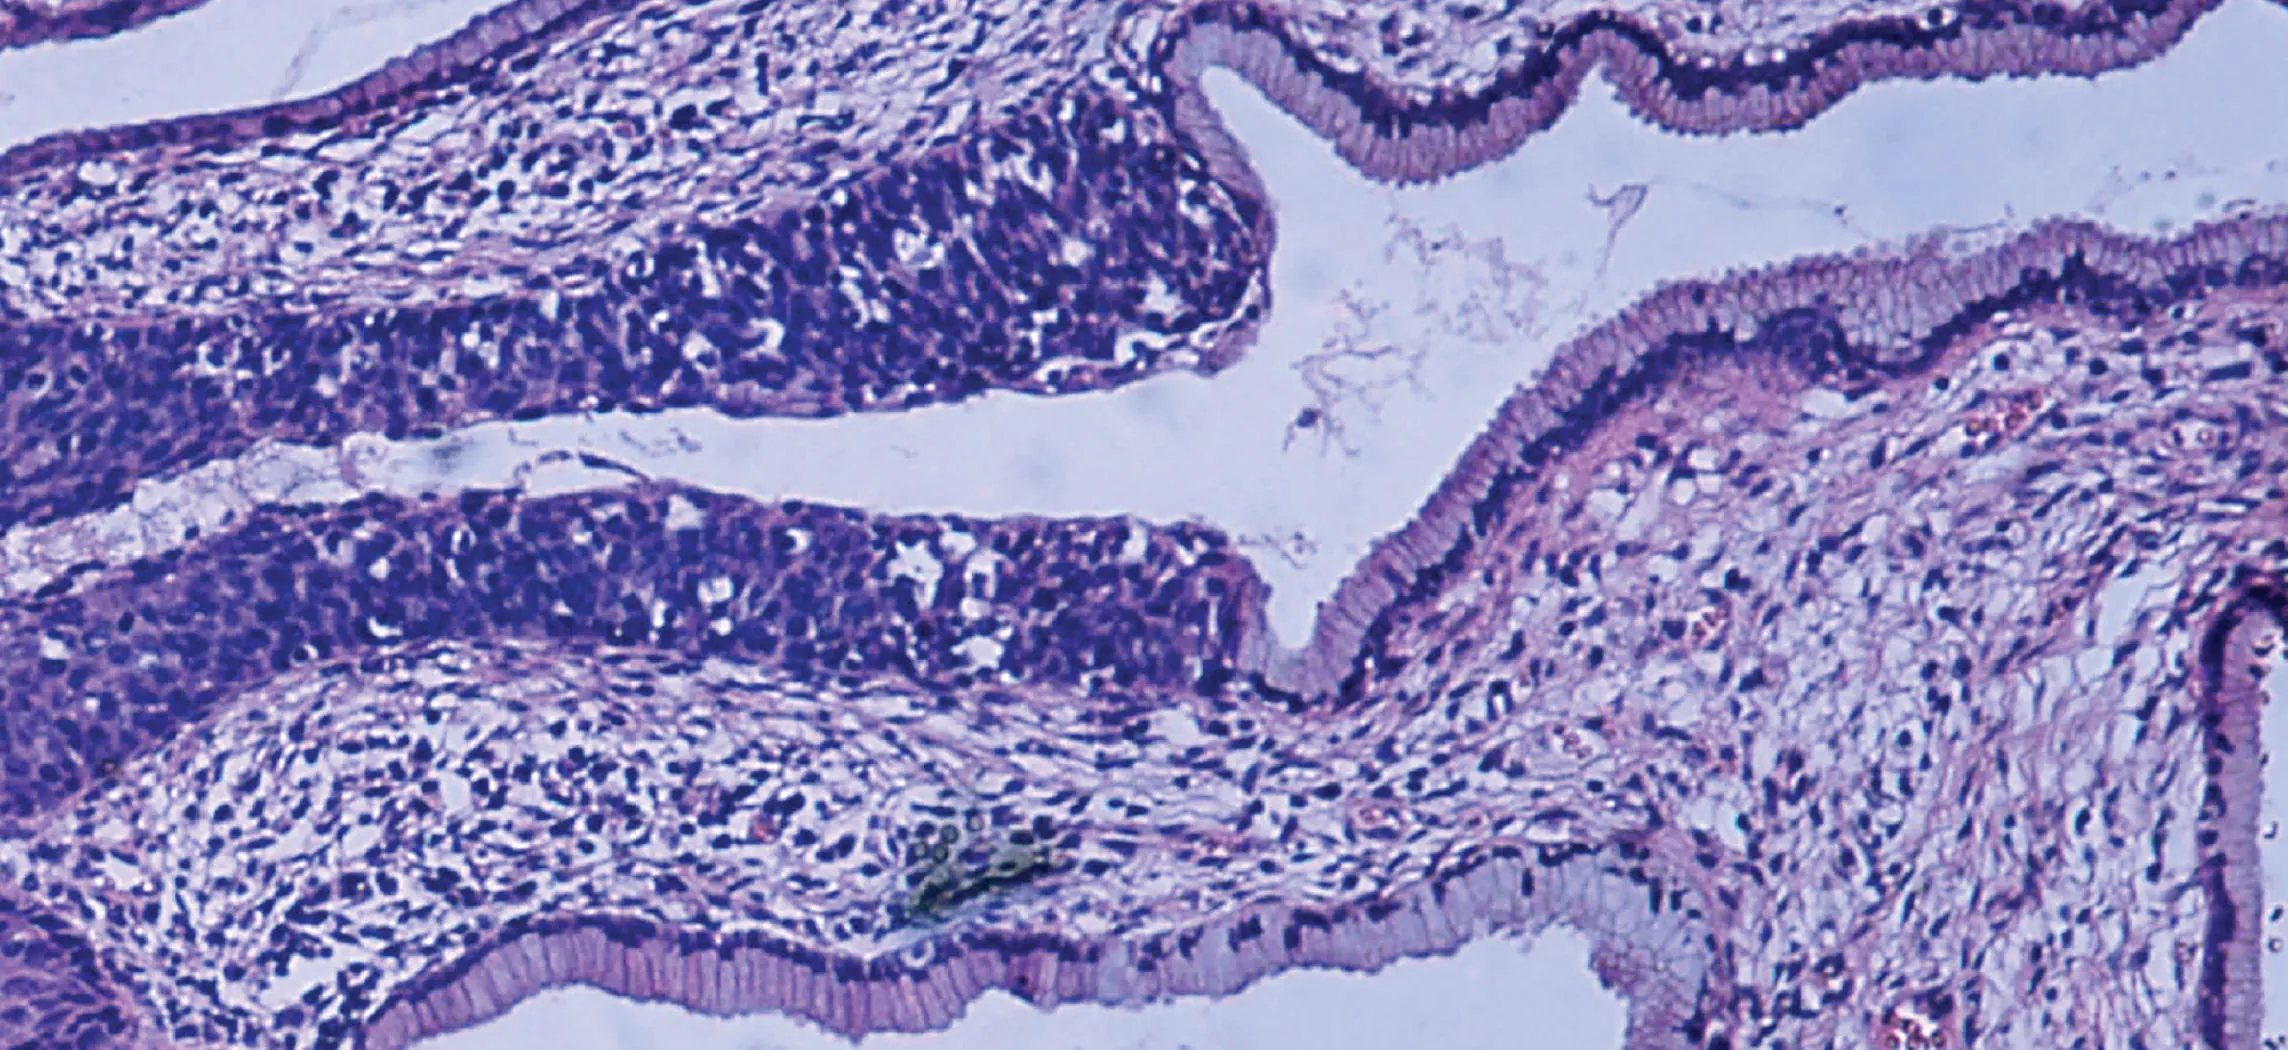

This micrograph shows tissue surrounding several empty spaces. The epithelial tissue occurs at the border between the rest of the tissue and the empty spaces. The normal epithelium is composed of rectangular-shaped cells neatly organized side by side. Dark purple nuclei are clear at the bottom of the epithelial cells, where they attach to the rest of the tissue. The abnormal epithelium appears as a tangled area of purple nuclei, much thicker than the normal epithelium although no distinct cells are discernible.

Figure 4.1 Micrograph of Cervical Tissue This figure is a view of the regular architecture of normal tissue contrasted with the irregular arrangement of cancerous cells. (credit: “Haymanj”/Wikimedia Commons)

The body contains at least 200 distinct cell types. These cells contain essentially the same internal structures yet they vary enormously in shape and function. The different types of cells are not randomly distributed throughout the body; rather they occur in organized layers, a level of organization referred to as tissue. The micrograph that opens this chapter shows the high degree of organization among different types of cells in the tissue of the cervix. You can also see how that organization breaks down when cancer takes over the regular mitotic functioning of a cell.